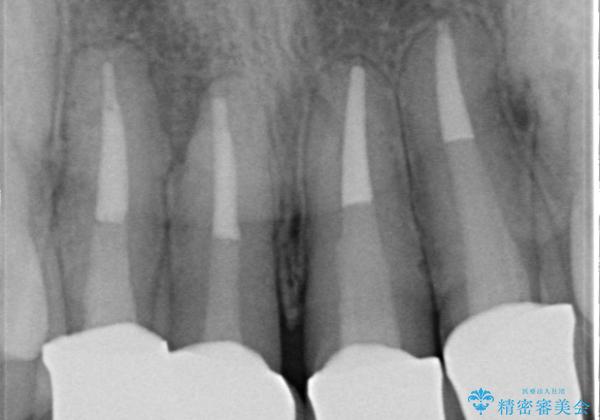

- 20年前に治療した前歯のセラミッククラウンが老朽化し見た目の改善を求めて来院されました。

不十分な根管治療を含めたセラミッククラウンのやりかえ治療を計画します。

- 52万円(仮歯・ファイバーコア・ジルコニアクラウン×4)費用は治療当時の料金となります